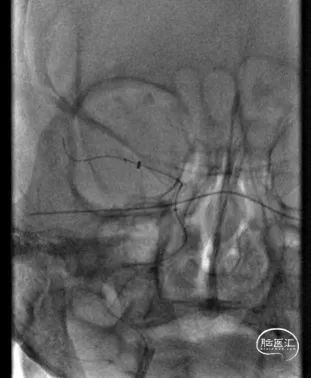

DSA造影见右侧大脑中动脉M1中段以远闭塞,ACA向MCA区域仅少量代偿。Sofia Plus在Headway21导管及Transend导丝引导下,很顺畅通过虹吸段等部位,到达M1中段。

采用ADAPT技术,血流快速复通;最右图为Sofia Plus导管前端及取出血栓。